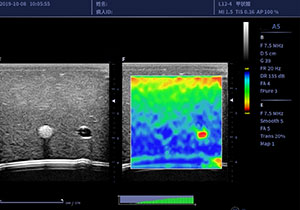

弹性成像ELASTOGRAPHY IMAGING

扩展成像技术